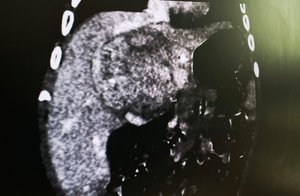

Пухлину виявили ще у 4 місяці, коли Демʼянчик перестав їсти, втратив вагу й зблід. У Лікарні Святого Миколая, де діє єдиний на західній Україні Центр холестатичних захворювань у дітей, діагностували майже повне ураження печінки — пухлина займала 8 з 12 сантиметрів довжини органу.

Хіміотерапія частково зменшила пухлину, але загроза життю залишалась. Єдиним шансом стала ALPPS — рідкісна операція, під час якої лікарі штучно стимулюють ріст здорової частини печінки. У Демʼянчика залишилось лише 15% функціональної тканини — і медики вирішили ризикнути.